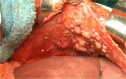

Results: Fifty-seven patients were included, 38 (67%) with diaphragmatic involvement; in 10 cases (18%), diaphragmatic resection was required. Optimal cytoreduction (OCR) was obtained in 49 cases (86%). The PCI was >10 in 31 cases (54%). Respiratory complications occurred in 10 cases (18%) and mortality in 3 (5%). Disease-free survival rate in 3 years was 53%, being 87% in cases without diaphragmatic involvement. The overall survival rate in 3 years is 46%, 83% in the cases without diaphragmatic involvement and 27% in cases with affectation (p<0.05). In cases of OCR, 3 year survival rate was 65%. In the multivariate analysis for the overall survival of cases with OCR, the only independent prognostic factor found was the operative PCI. A strong correlation was found between the total PCI and the diaphragmatic PCI (p<0.001). With a PCI >10, virtually all cases will present diaphragmatic involvement (p<0.05).

Conclusion: The tumor burden is different in stages III and IV of advanced ovarian cancer and the PCI is an effective method to quantify it. The PCI constitutes an independent prognostic factor for the advanced stages of ovarian cancer. A PCI >10 constitutes a useful prognostic factor of the affectation and forces the surgeon to thoroughly review both diaphragms.